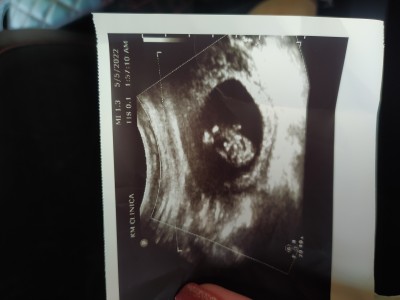

Kizlar sizce cinsyet ne tahmin yapin.

Kizlar sizce cinsyet ne

12.4

Bana kız gibi geldi..

İki tane çocuğum var bir kız bir erkek ve bebeğin duruşu falan kızıma benzettim oyuzden yoksa doktor değilim ya hem sizi ilgilendirmiyor ki zaten karşı taraf da burda doktor olmadığını biliyor o da tahmin istiyor

Dun oyrendm erkek